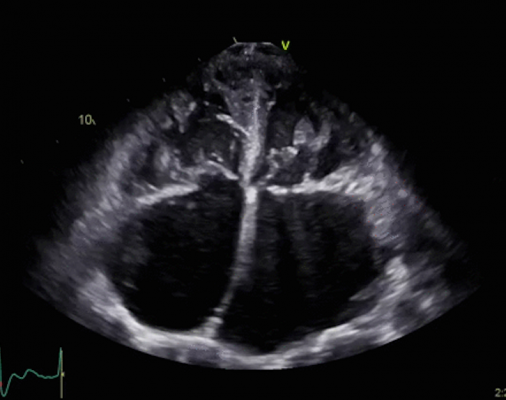

Physicians today need imaging studies that provide high-quality diagnostic capabilities no matter where the patient is, from the inpatient hospital setting to the outpatient and point of care settings. Bay Labs applies AI to cardiovascular imaging to help in the diagnosis and management of heart disease. An echocardiographic exam is the gateway to cardiovascular disease diagnosis and a key to disease management and appropriate timing of intervention. The company’s deep learning technology, a type of AI algorithm, is designed to help medical professionals of all skill levels perform and interpret echocardiograms and may improve the treatment of heart diseases. Bay Labs has partnered with the Minneapolis Heart Institute and Allina Health, Northwestern Medicine, Duke University School of Medicine and cardiologists at Stanford University to develop, test and validate deep learning algorithms for echocardiography.